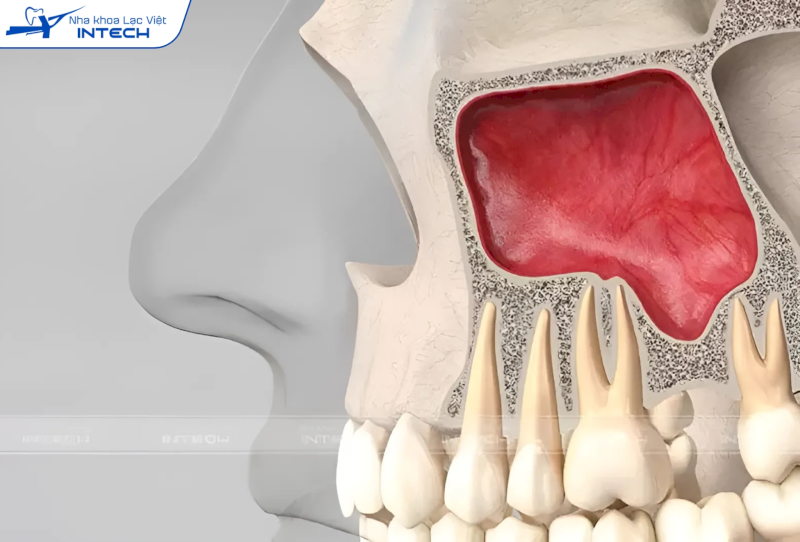

Mất răng khiến khoang xoang sa xuống, dẫn đến thiếu thể tích xương để cấy ghép Implant hàm trên

Xoang hàm trên là một khoang rỗng nằm trong xương hàm trên, kéo dài từ vùng răng số 4 đến răng số 8. Xoang này đóng vai trò quan trọng trong việc thông khí, lọc bụi bẩn và cộng hưởng âm thanh. Khi cô chú/anh chị mất răng hàm trên trong thời gian dài, xương hàm tại vị trí đó có xu hướng tiêu biến, dẫn đến việc xoang hàm mở rộng và sa xuống.

Sự thay đổi này làm giảm chiều cao xương hàm, khiến vùng xương không đủ thể tích để đặt trụ Implant một cách an toàn và ổn định. Do đó, việc nâng xoang là cần thiết để tái tạo chiều cao xương hàm, tạo nền tảng vững chắc cho quá trình cấy ghép Implant.

Nâng xoang giúp hàm trên có đủ thể tích xương để đảm bảo trụ Implant được cấy ghép vững chắc